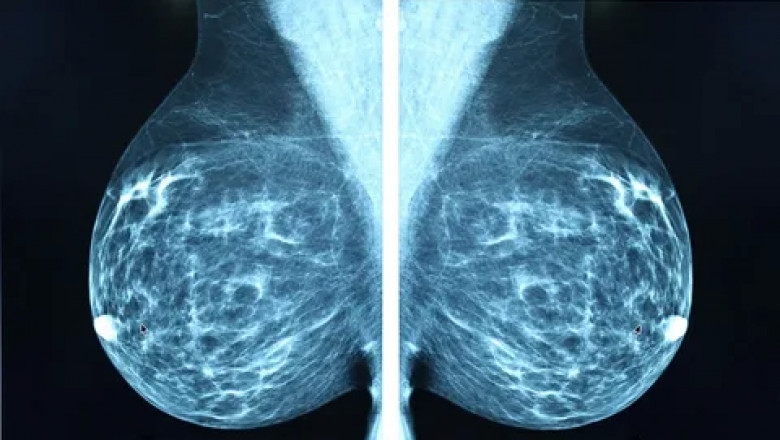

This technique, which is a subset of mammography, creates 3D breast information by rotating the X-ray tube around a small angular from the compressed breast tissue. DBT pictures are produced by repeatedly exposing breast tissue to different angles and reconstructing the results as half-millimeter slices. The radiation dose to the patient is increased by 20% using this procedure, according to several studies, yet the likelihood of finding cancer rises by around 15–30%, and the likelihood of recall falls by about 15-20% Tom synthesis' key benefit is the ability to detect masses and lesions that may not be visible on a traditional mammogram because of overlap with dense breast tissue. Tom synthesis has a high sensitivity and a low rate of false-positive detections. Hence, the this approach will result in more precise staging of Breast Imaging. DBT is more effective than traditional mammography for detecting non-calcified lesions, though classified lesions also show comparable or superior outcomes. The recurrence rate has been decreased by up to 30% in the USA by combining digital mammography and breast tom synthesis. However, compared to conventional digital mammography, the radiation exposure in DBT is 8% higher. In conclusion, the main drawback of this approach is its low sensitivity in the identification of microcalcifications. DBT results in a 27% increase in breast cancer diagnoses and a 15% decrease in false-positive results. DBT often performs better in diagnosis and screening than mammography. However, it decreases the patient's capacity to recall